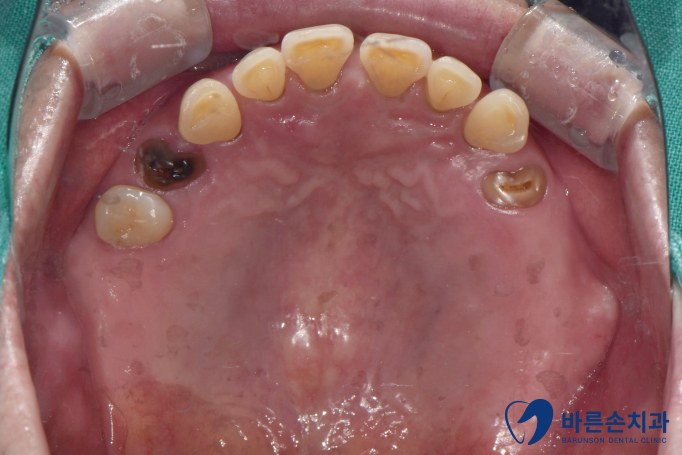

윗 어금니들이 다 빠지거나 부러진 환자분 께서 내원하셨습니다.

사진을 보시면 치아가 부러져서

작은 어금니는 뿌리만 남아있고

큰 어금니는 이미 상실되어있습니다..